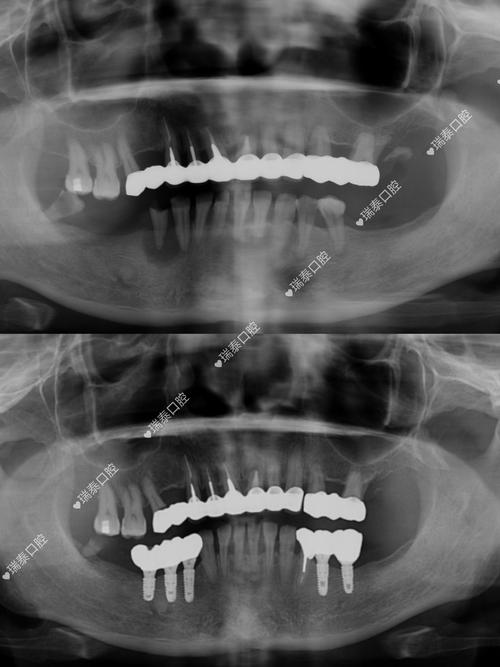

种植牙相当于在牙槽骨中“打桩”,牙槽骨的高度、宽度、密度直接决定种植体能否稳定植入和长期使用,普通X光片(如根尖片、曲面断层片)虽能显示骨大致情况,但存在明显局限性:它是二维重叠影像,无法准确测量骨的垂直高度和水平宽度,尤其对后牙区(如下颌后牙、上颌后牙)的骨量评估误差较大,可能因角度偏差导致实际骨量比预估更少。

而CT(口腔种植常用锥形束CT,简称CBCT)能生成三维立体图像,可精确测量牙槽骨的骨高度(如种植区距离上颌窦底、下颌神经管的距离)、骨宽度(是否足够容纳种植体直径)、骨密度(骨密度过低会影响种植体骨结合),若上颌后牙区牙槽骨高度不足5mm,种植体可能穿入上颌窦,引发感染或种植体失败;若下颌骨宽度不足5mm,植入种植体时可能损伤下牙槽神经,导致下唇麻木,CT能清晰显示这些关键数据,帮助医生判断是否需要植骨、骨增量,或选择更短的种植体,避免盲目手术。

- 植入角度设计:对于牙列不齐或邻牙倾斜的患者,CT可显示邻牙牙根与种植区的位置关系,设计避开邻牙牙根的植入角度,避免损伤邻牙;

相比之下,普通X光片无法提供角度和三维位置信息,医生仅凭经验设计方案,可能导致种植体位置偏差,影响修复体的美观和功能(如种植体倾斜导致假牙咬合异常)。